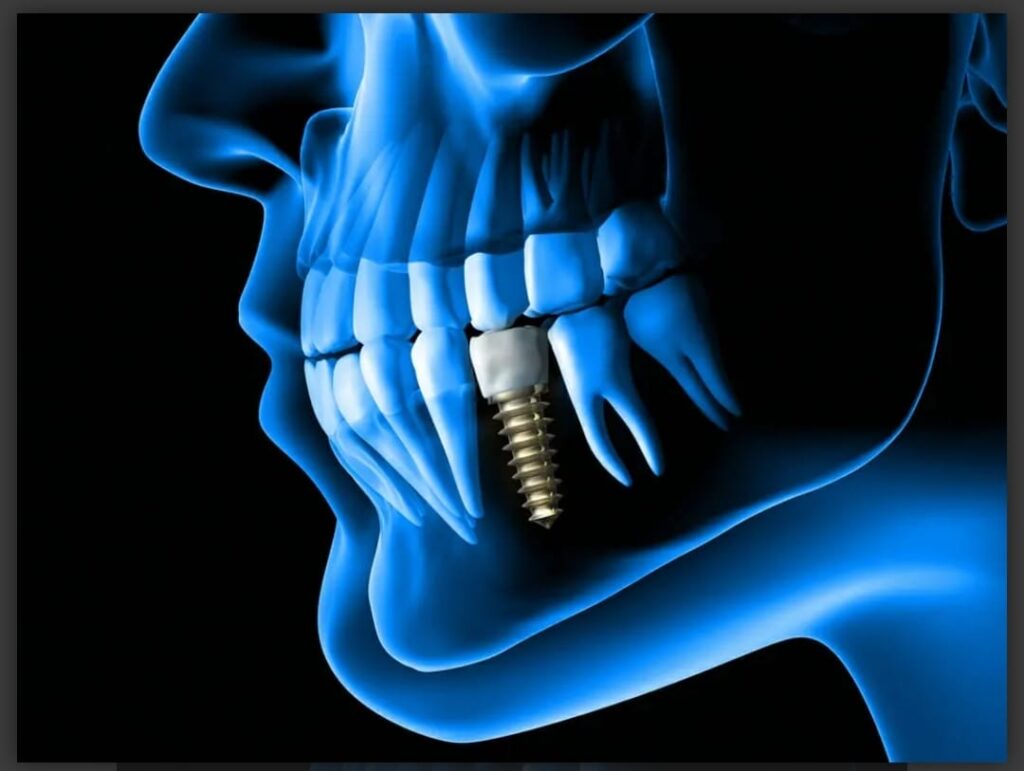

Dental Implants

Dental implants are a long-term solution to tooth loss, providing a natural-looking smile and restoring proper mouth function. Our expert team ensures precise placement and comfortable recovery.